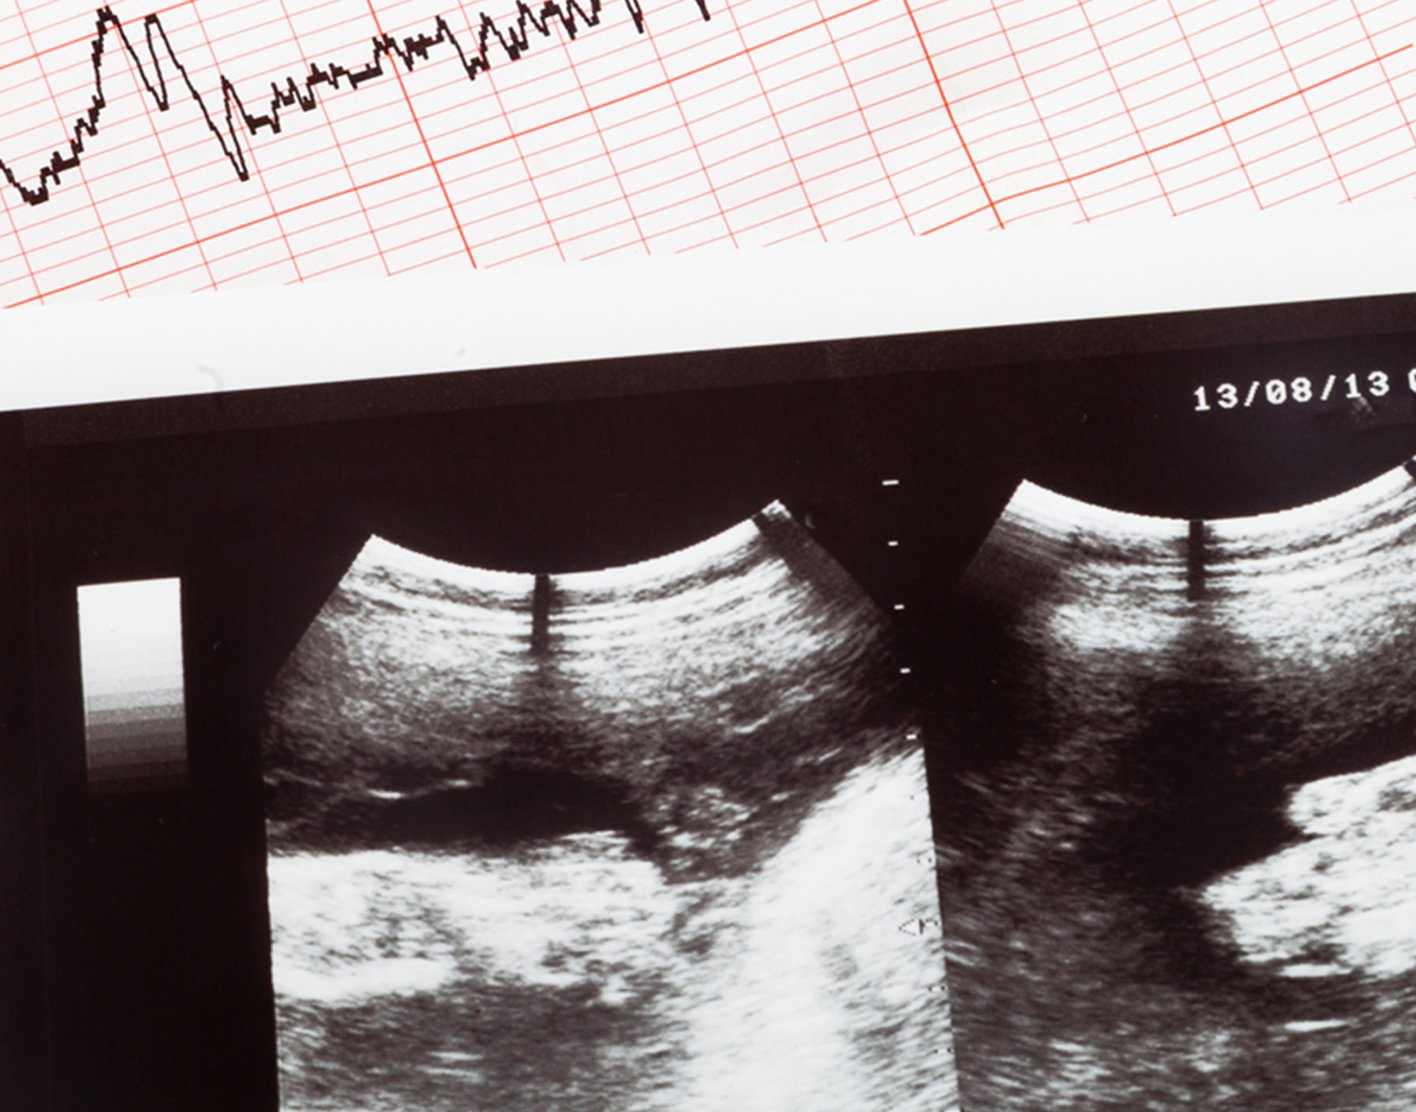

Fetal echocardiography is a test that is done while the baby is still in the womb. It is most often done during the second trimester of pregnancy. This is when a woman is about 18 to 24 weeks pregnant.

In an abdominal ultrasound, the person performing the test places a clear, water-based gel on your belly. A hand-held probe is moved over the area. The probe sends out sound waves, which bounce off the baby's heart and create a picture of the heart on a computer screen.

In a transvaginal ultrasound, a much smaller probe is placed into the vagina. A transvaginal ultrasound can be done earlier in the pregnancy and produces a clearer image than an abdominal ultrasound.

This test is done to detect a heart problem before the baby is born. It can provide a more detailed image of the baby's heart than a regular pregnancy ultrasound.